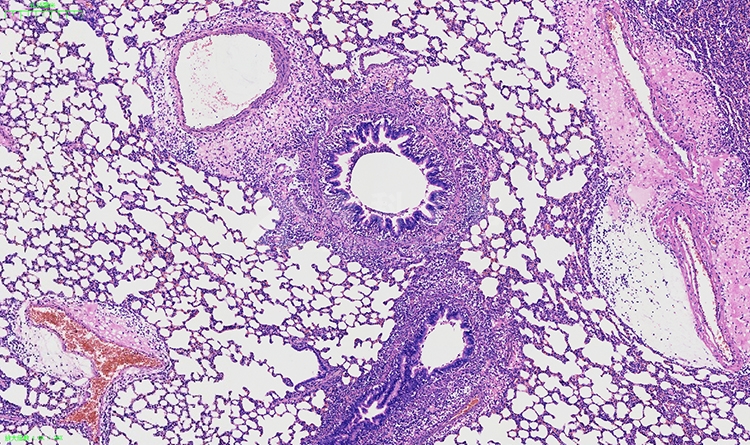

冰冻切片和染色是病理学检测中常用的技术手段,用于研究组织和细胞的结构、功能以及病变情况。以下将介绍冰冻切片和染色在病理学检测中的意义、应用方法以及对疾病诊断和研究的影响。

冰冻切片和染色在病理学检测中的意义重大。通过冰冻切片,可以快速地获取新鲜组织样本,并保留其原有的形态结构和细胞活性,为进一步的组织学观察提供了良好的基础。而染色则能够突出组织和细胞的特定结构和成分,使其更易于观察和分析。冰冻切片与染色相结合,可以为医生和研究人员提供丰富的信息,帮助他们诊断疾病、评估治疗效果以及进行病理学研究。

冰冻切片的制备方法相对简便快速。通常,将新鲜组织样本迅速冷冻并切割成薄片,再进行染色处理即可得到冰冻切片。这种方法不需要进行组织固定和蜡包埋等繁琐的步骤,省去了较长的处理时间,有利于快速获取与疾病相关的组织结构信息。

冰冻切片与常规石蜡包埋切片相比,具有优势和适用范围的差异。冰冻切片适用于需要快速诊断或组织活性分析的情况,如急性炎症、肿瘤边缘判定、免疫荧光染色等。而石蜡包埋切片则适用于需要进行长期保存、大规模观察和高度细致分析的研究中。

关于染色方法,常用的染色技术包括常规的血液染色(如伊红染色、嗜酸性染色等)、组织结构染色(如苏木精-伊红染色、伊红-金黄染色等)以及特殊染色(如免疫组化染色、核酸染色等)。这些染色方法能够使细胞和组织的结构、功能以及病变情况更加清晰可见,有助于对疾病进行定性和定量的分析。

综上所述,冰冻切片与染色在病理学检测中起着重要作用。它们能够提供新鲜组织样本的形态结构信息和细胞活性,帮助医生进行疾病诊断和治疗评估,同时也支持病理学研究的推进。通过冰冻切片和染色技术的应用,我们可以更加全面地了解疾病的发生机制和病理变化,为临床诊断和医学研究提供有力支持。